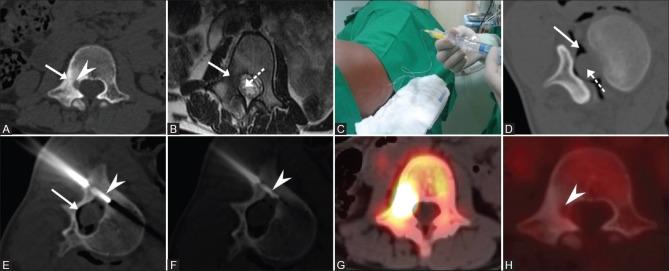

MATERIALS AND METHODS

This is a retrospective analysis of prospectively maintained data of 43 symptomatic osteoid osteoma patients who were treated by radiofrequency ablation (RFA). Forty out of 43 patients were naive cases and underwent primary treatment for osteoid osteoma with RFA, whereas 3 patients included in the study underwent RFA for local recurrence after having undergone surgical treatment. Diagnosis was based on clinical and characteristic imaging findings, and biopsy was done for cases with atypical presentation. Pre and post procedure Visual Analog Score (VAS) was documented in all cases. Monopolar RFA system was used in all patients, and the electrode was placed within the lesion nidus under CT guidance coaxially through 11G introducer needle. Ablation was performed at 90° C for 5 min.

材料与方法

这是一项对43例接受射频消融(RFA)治疗的有症状骨样骨瘤患者的前瞻性维护数据进行的回顾性分析。43例患者中有40例为初发病例,接受了RFA治疗骨样骨瘤的初次治疗,而纳入研究的3例患者在接受手术治疗后因局部复发接受了RFA治疗。诊断基于临床和特征性影像学表现,对于表现不典型的病例进行了活检。所有病例均记录了术前和术后视觉模拟评分(VAS)。所有患者均使用单极RFA系统,电极在CT引导下通过11G穿刺针同轴放置在病变巢内。在90°C下进行5分钟的消融。